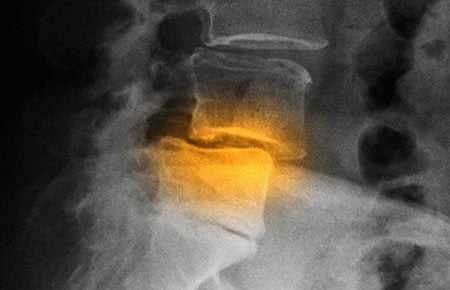

- неравномерное сужение межпозвонковых щелей в сегментах L – L в задних отделах;

- субхондральный склероз в телах L позвонков;

- остроконечные остеофиты фиксируются по передней поверхности тел L позвонков;

- умеренное смещение кпереди тел L позвонков;

- некоторое смещение кзади тел L позвонков;

- определяется умеренно выраженная деформация тел L позвонков;

- определяется неровность, нечеткость замыкательных пластинок тел L позвонков за счёт дегенеративно-атрофических изменений отражающих распад межпозвонкового диска с разрушением замыкающих пластинок тел позвонков и внедрением элементов распавшегося диска в тела позвонков в виде мелких узелков Поммера, что свидетельствует о функциональной неполноценности межпозвонковых дисков сегментов L – L ;

- дегенеративно - реактивные изменения: в виде остеофитов (как проявление компенсаторной приспособительной реакции в позвонках на нагрузку, которая падает на измененный диск) определятся в телах L позвонков; в виде субхондрального склероза определяются в телах L позвонков;

- скошенность углов тел позвонков, которая может быть обусловлена дегенеративным процессом в краевом канте (лимбус) тела позвонка определяется в телах L ;

- хрящевые узлы тел позвонков (грыжи Шморля) определяются в телах L и являются одним из проявлений дистрофических поражений в двигательных сегментах позвоночника и свидетельствуют о пролабировании фрагментов межпозвоночного диска в тело позвонка;

- признаки нестабильности (нарушение динамической функции поясничного отдела позвоноч-ника) в сегментах L – L , что свидетельствует о дистрофических изменениях в дисках L – L в фазе снижения их тургора.